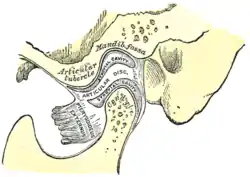

| Sagittal section of the articulation of the mandible. | |

The joint involved with jaw dislocation is the temporomandibular joint (TMJ). This joint is located where the mandibular condyles and the temporal bone meet.[7][8] Membranes that surround the bones help during the hinging and gliding of jaw movement. For the mouth to close it requires the following muscles: the masseter, temporalis, and medial pterygoid muscle. For the jaw to open it requires the lateral pterygoid muscle.[8]

There are four different positions of jaw dislocation: posterior, anterior, superior and lateral. The most common position is anterior, while the other types are rare. Anterior dislocation shifts the lower jaw forward if the mouth excessively opens. This type of dislocation may happen bilaterally or unilaterally after yawning. The muscles that are affected during anterior jaw dislocation are the masseter and temporalis which pull up on the mandible and the lateral pterygoid which relaxes the mandibular condyle. The condyle can get locked in front of the articular eminence. Posterior dislocation is possible for people who get injured by being punched in the chin. This dislocation will push the jaw back affecting the alignment of the mandibular condyle and mastoid. The external auditory canal may be fractured. Superior dislocations occur after being punched below the mandibular ramus as the mouth remains half-open. Since great force occurs in a punch, the angle of the jaw will be forced upward moving towards the condylar head. This can result in a fracture of the glenoid fossa and displacement of the condyle into the middle cranial fossa, potentially injuring the facial and vestibulocochlear nerves and the temporal lobe. Lateral dislocations move the mandibular condyle away from the skull and are likely to happen together with jaw fractures.[8][9]